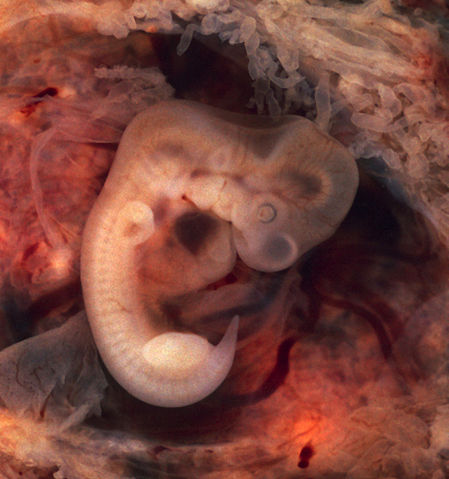

Human Embryo (7th week of pregnancy, 5th week p.o.) This photo of an opened oviduct with an ectopic pregnancy features a spectacularly well preserved 10-millimeter embryo. It is uncommon to see any embryo at all in an ectopic, and for one to be this well preserved (and undisturbed by the prosector's knife) is quite unusual.

Even an embryo this tiny shows very distinct anatomic features, including tail, limb buds, heart (which actually protrudes from the chest), eye cups, cornea/lens, brain, and prominent segmentation into somites. The gestational sac is surrounded by myriad chorionic villi resembling elongated party balloons. This embryo is about five weeks old (or seven weeks in the biologically misleading but eminently practical dating system used in obstetrics). The photo was taken on Kodak Elite 200 slide film, with a Minolta X-370 camera and 100mm f/4 Rokkor bellows lens at near-full extension. The formalin-fixed specimen was immersed in tap-water and pinned to a tray lined with black velvet. The exposure was 1/4 second at f/8. |